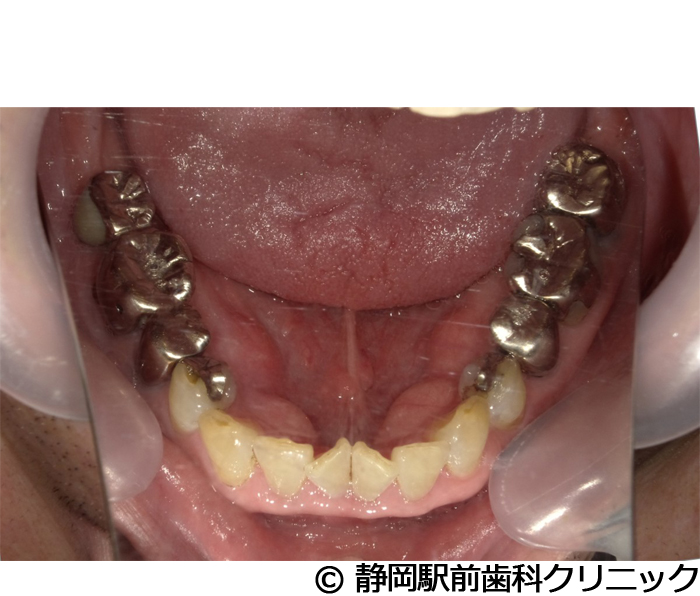

【症例5】全顎的インプラントとセラミックによる審美補綴

- 治療前

- 治療後

- 治療名

- 全顎的インプラントとセラミックによる審美補綴

- 費用

- 1,800,000円(税込)

- 期間

- 1年6ヵ月

治療内容

患者様の症状

-

全体的に歯がないため、噛めない。インプラント治療希望。

治療方法

全体的に残根は抜歯を行い、術前にCTを撮影し緻密に治療計画を立てた。インプラント埋入はブロックごとに行い、噛み合わせの調整を重ねた後、人工歯を被せて咬合と審美の回復を行いました。

治療結果

しっかり奥歯で食べ物を噛み切ることができるようになり、何でも食べることができるようになったと喜んでいただくことができました。口元を気にせずに笑うこともできるようになり、見た目もキレイになったとご満足いただけました。

※治療結果は個人差があります。

治療を行う上での注意点(リスク・副作用)

術後は、出血、腫れ、痛みなどが出る可能性があります。